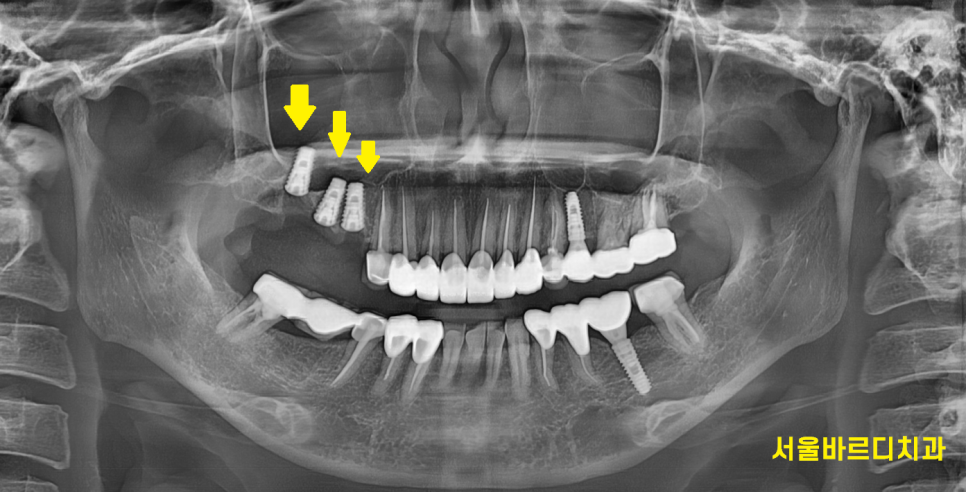

240415

발치 후 임플란트를 해주었습니다.

기존에는 치아 1개가 없지만

양 옆 치아를 깎아서 보강해준 브릿지 형태였지만

이번에는 부러지거나 탈나지 않게

임플란트 치료로

모자른 개수 없게 치아 원래 개수대로

만들어주었습니다.

240208

수술 진단 시 문제가

상악동과 근접한거였는데요.

임플란트 길이가 5.4mm정도 부족한 것은

상악동 거상을 동반한 뼈이식으로 해결하였습니다.